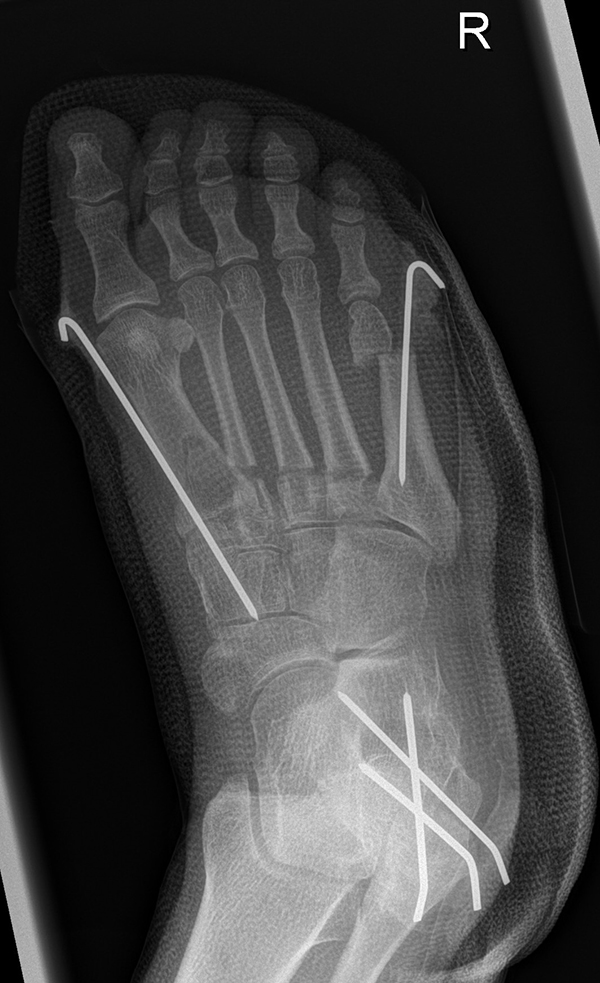

Zusätzlich schränken Wachstumsfugen die Wahl der Osteosynthese ein. Eine die Fuge kreuzende Osteosynthese ist ausschließlich mit Kirschner-Drähten möglich (Abb. 3).

Abb. 3 a-j: Beispiel einer Calcaneusverschiebeosteotomie mit offenen Wachstumsfugen und der entsprechenden Osteosynthese mit Kirschner Drähten. Lokalisation der Osteotomie (a), Lage der Fräse (b-d), Drahtlage mehrere Ansichten (e-h), Heilung der Osteotomie 4 Wochen postoperativ und Entfernung der Drähte (i-j).

Calcaneus-Osteotomie

Die minimalinvasive Calcaneusverschiebeosteotomie bietet eindeutige Vorteile gegenüber dem offenen Verfahren, sodass wir bei Kindern und Jugendlichen nahezu keine offene Verschiebeosteotomie mehr durchführen. Am Calcaneus liegt die offene Wachstumsfuge dorsal. Bei der Durchführung müssen Schenkel der V-förmigen Osteotomie daher etwas steiler angelegt werden, in einem stumpfen Winkel (siehe Abb. 3 a-j). Für die Osteotomie liegen unsere Patienten auf dem Rücken und der BV wird für die exakte Seitaufnahme eingestellt. Der Fuß lagert auf einem hohen OP-Kissen und die Osteotomie kann bequem mit einem langen Kirschner-Draht und einem sterilen Stift angezeichnet werden (Abb. 15).